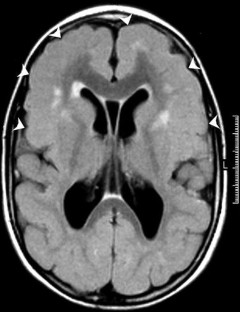

The malformations of the cerebral cortex represent a major cause of developmental disabilities, severe epilepsy and reproductive disadvantage. The advent of high-resolution MRI techniques has facilitated the in vivo identification of a large group of cortical malformation phenotypes. Several malformation syndromes caused by abnormal cortical development have been recognised and specific causative gene defects have been identified. Periventricular nodular heterotopia (PNH) is a malformation of neuronal migration in which a subset of neurons fails to migrate into the developing cerebral cortex. X-linked PNH is mainly seen in females and is often associated with focal epilepsy. FLNA mutations have been reported in all familial cases and in about 25% of sporadic patients. A rare recessive form of PNH due ARGEF2 gene mutations has also been reported in children with microcephaly, severe delay and early seizures. Lissencephaly-pachygyria and subcortical band heterotopia (SBH) are disorders of neuronal migration and represent a malformative spectrum resulting from mutations of either LIS1 or DCX genes. LIS1 mutations cause a more severe malformation in the posterior brain regions. Most children have severe developmental delay and infantile spasms, but milder phenotypes are on record, including posterior SBH owing to mosaic mutations of LIS1. DCX mutations usually cause anteriorly predominant lissencephaly in males and SBH in female patients. Mutations of DCX have also been found in male patients with anterior SBH and in female relatives with normal brain magnetic resonance imaging. Autosomal recessive lissencephaly with cerebellar hypoplasia, accompanied by severe delay, hypotonia, and seizures, has been associated with mutations of the reelin (RELN) gene. X-linked lissencephaly with corpus callosum agenesis and ambiguous genitalia in genotypic males is associated with mutations of the ARX gene. Affected boys have severe delay and seizures with suppression-burst EEG. Early death is frequent. Carrier female patients can have isolated corpus callosum agenesis. Among several syndromes featuring polymicrogyria, bilateral perisylvian polymicrogyria shows genetic heterogeneity, including linkage to chromosome Xq28 in some pedigrees, autosomal dominant or recessive inheritance in others, and an association with chromosome 22q11.2 deletion in some patients. About 65% of patients have severe epilepsy. Recessive bilateral frontoparietal polymicrogyria has been associated with mutations of the GPR56 gene. Epilepsy is often present in patients with cortical malformations and tends to be severe, although its incidence and type vary in different malformations. It is estimated that up to 40% of children with drug-resistant epilepsy have a cortical malformation. However, the physiopathological mechanisms relating cortical malformations to epilepsy remain elusive.

Fig. 1

Fig. 2

Fig. 3

Fig. 4

Fig. 5

Fig. 6

Fig. 7